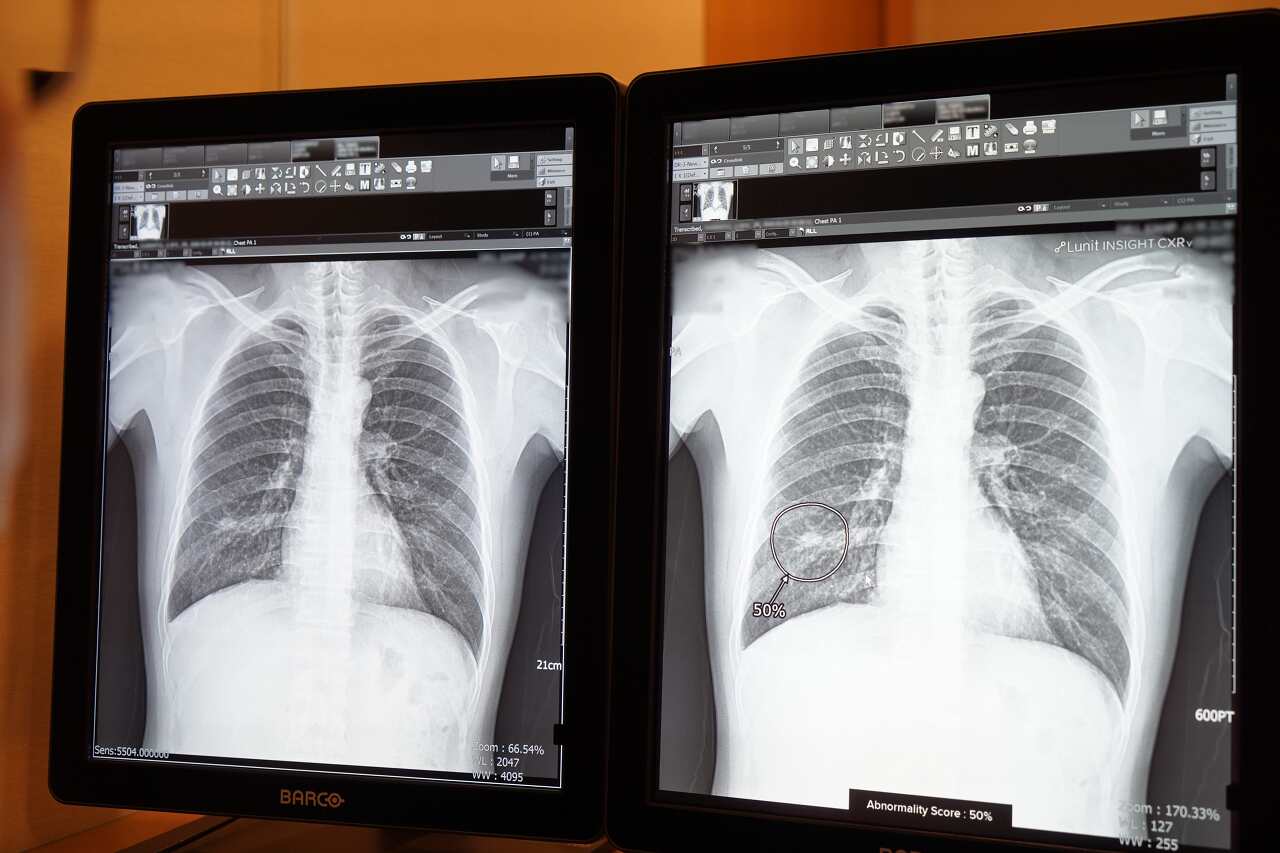

체결된 구매계약 제품은 루닛의 인공지능 제품군 중 하나인 '루닛 인사이트 CXR'(Lunit INSIGHT CXR)이다. 이 제품은 루닛의 독자적인 인공지능 기술을 바탕으로 흉부 엑스레이 영상을 분석해 의사들의 빠르고 정확한 판독과 진단을 보조할 목적으로 설계됐다.

방식은 환자의 흉부 엑스레이 사진을 수 초 내로 분석해, 각 질환 의심 부위와 의심 정도를 색상 등으로 자동 표기한다. 단 몇 초 만에 폐 결절, 폐 경화, 기흉을 포함한 주요 비정상 소견을 97~99%의 정확도로 검출해낸다는 것이 장점이다.

루닛 인사이트 CXR'(Lunit INSIGHT CXR) 가동 모습. 사진 루닛